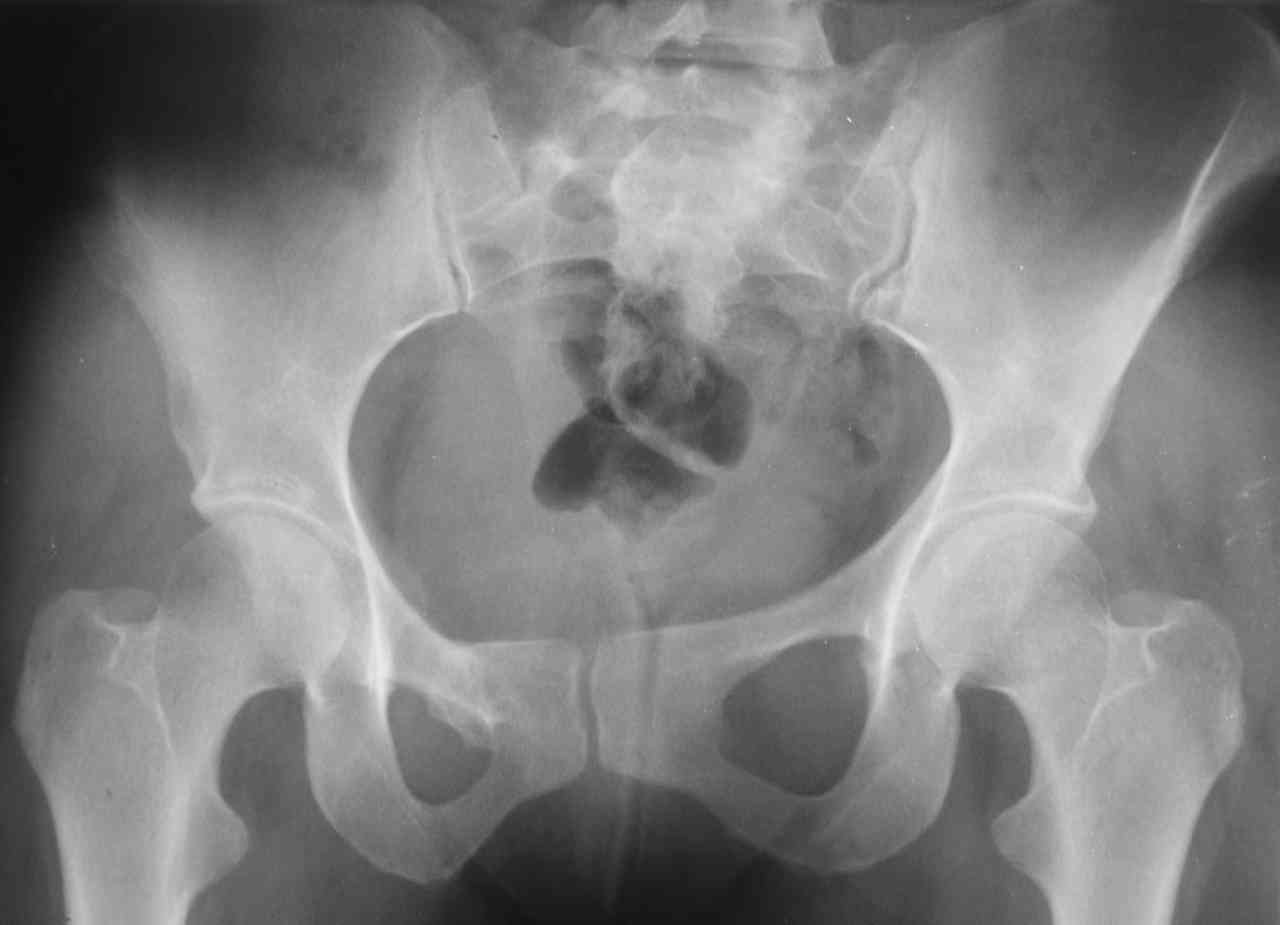

К нам в клинику поступила пациентка 30 лет с диагнозом: Постравматическая ротационная стабильная деформация тазового кольца.

Относительное укорочение левой н\конечности на 1 см. Левосторонний компенсаторный сколиоз 2 ст. Болевой синдром.

С марта 2003 года жалуется на боли в тазу, ппояснице усиливающиеся при движении. В настоящее время жалобы на боли в области крестца, КПС больше слева, в пояснично-крестцовом отделе позвоночника. неприятные ощущения, щелчок при выпрямлении правого тазобедренного сустава из положения полного сгибания. боли в тазу появляются при ходьбе ч\з 100 м, так же при вставании из положения сидя, после сидения в течении 2-3 часов. при ходьбе более 100 м появпяется зябкость стоп больше справа. ходит при помощи трости в правой или в левой руке. без трости боли появляются сразу после начала ходьбы.

Объем движений в тазобедренных суставах полный. правый КПС заблокирован.

симптомы натяжения с обеих сторон отрицательны. С 2003г. лечится консервативно, получала ЛФК, массаж, физиолечение - без эффекта. в 2005г. лечилась в санатории с ортопедическим уклоном, получала плавание в минеральной воде, магнитотерапия, массаж, ЛФК. отмечала умеренное улучшение в течении 2 недель. Вопросы: надо ли оперировать, т.е. устранять относительное укорочение левой н\конечности и как?Если не оперировать, то как лечить консервативно? Р-граммы, КТ прилогаются.